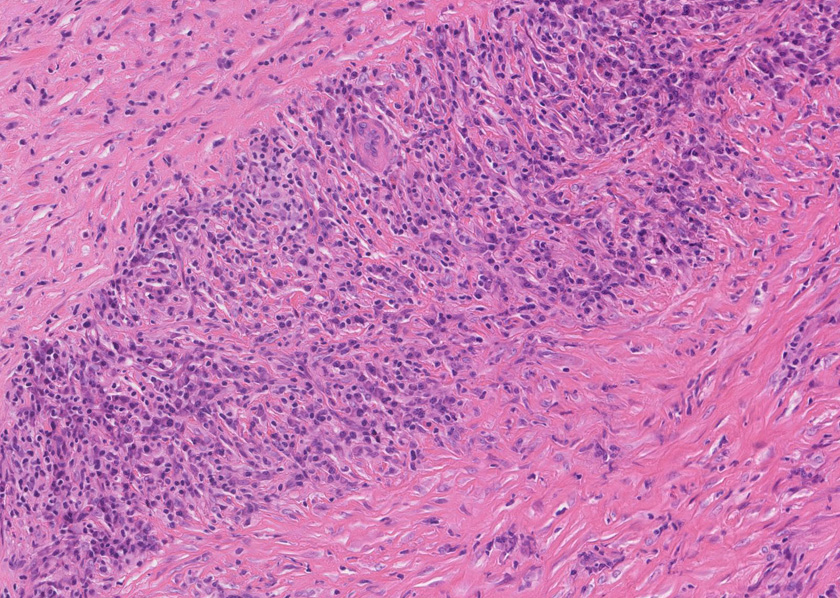

膵腺房間質にリンパ球, 形質細胞, 好中球の炎症細胞浸潤が認められる。

pancC.jpg

線維化組織に類円, 葉巻型淡明な核の紡錘型細胞が増生している。免染SMA陽性。血管周囲に慢性炎症あり。

組織像は膵腫瘤B, Cと同じくinflammatory myofibroblastic tumorである。島状に形質細胞主体の慢性炎症が強い。腹膜腫瘤には腺管は認められない。